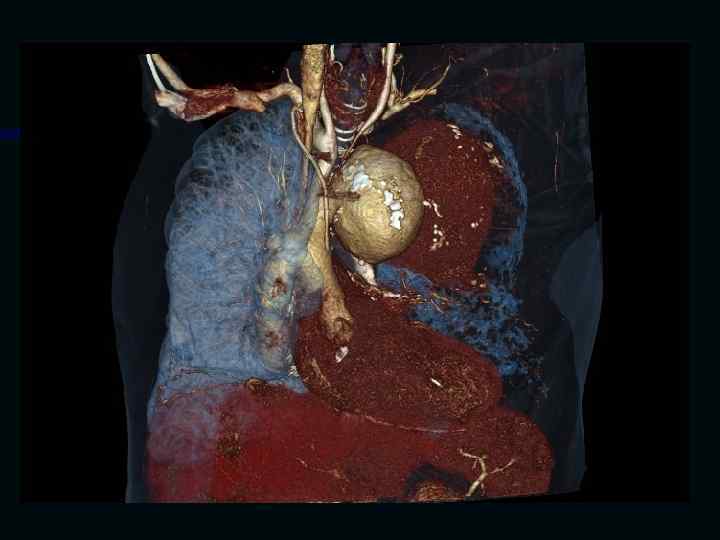

Исследование сосудов грудной клетки

Исследование сосудов брюшной полости